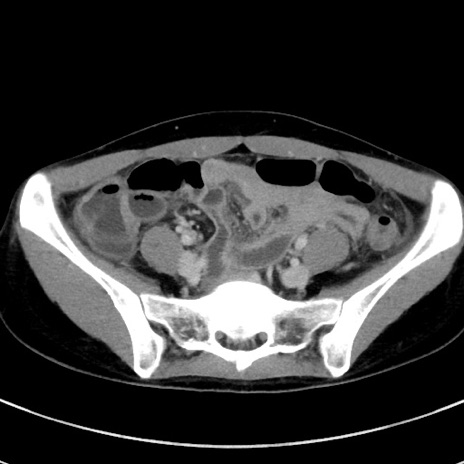

症例17(横断像)

【症例】20歳代女性

【主訴】嘔吐、下腹部痛

【現病歴】昨日夕食後に嘔吐し下腹部痛が出現。本日になっても嘔吐持続し改善しないため来院。

【身体所見】意識清明、BT 37.2℃、BP 108/67mmHg、腹部:平坦、やや硬、下腹部正中から右にかけて圧痛あり、反跳痛軽度あり、tapping pain(+)。

【データ】WBC 13600、CRP 14.94